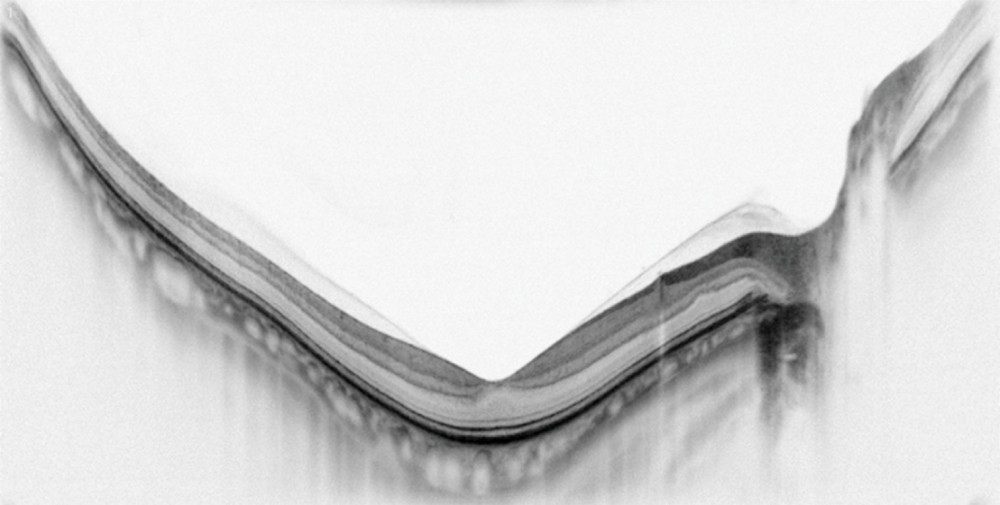

Meibography

The tears are the first thing light strikes when it enters your eye. Assessing tear quality and tear gland density is very helpful for your doctor to help take care of your vision and eye comfort. The meibomian glands in the eyelids make critical components of the tears and can be damaged by screen time, age, diet, and air pollution, leading to dry eye or eyelid inflammation. Early detection can allow intervention to save your meibomian glands, help reduce dry eye, and protect the surface of the eye for years to come.